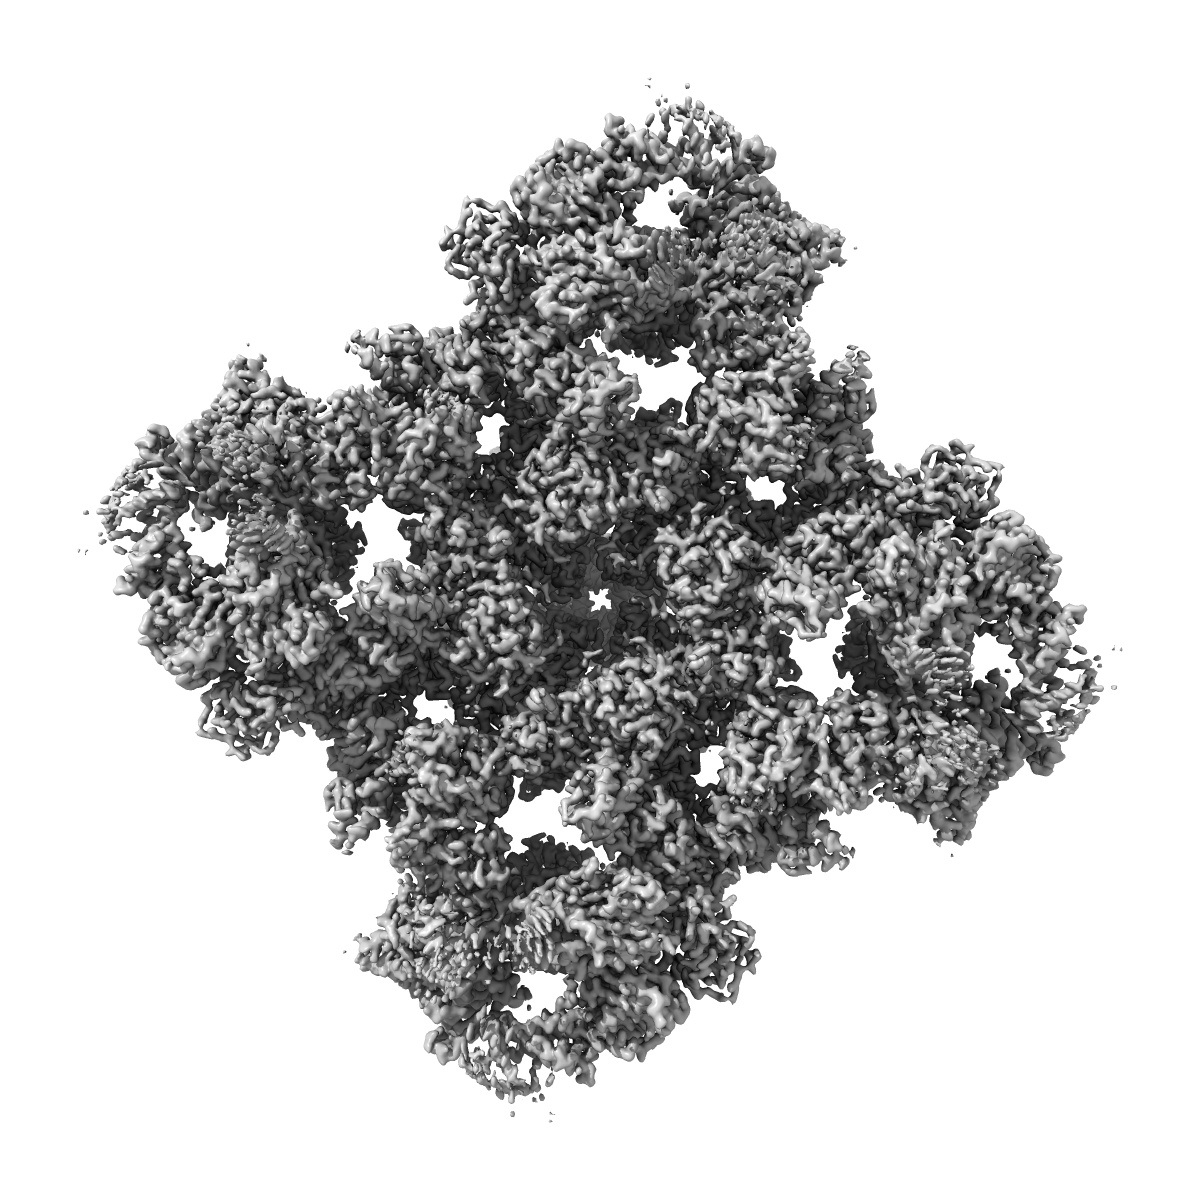

EMD-26205

A drug and ATP binding site in type 1 ryanodine receptor

Single-particle2.45 Å

Sample: Ryanodine receptor 1 complex with calmodulin and calstabin-1